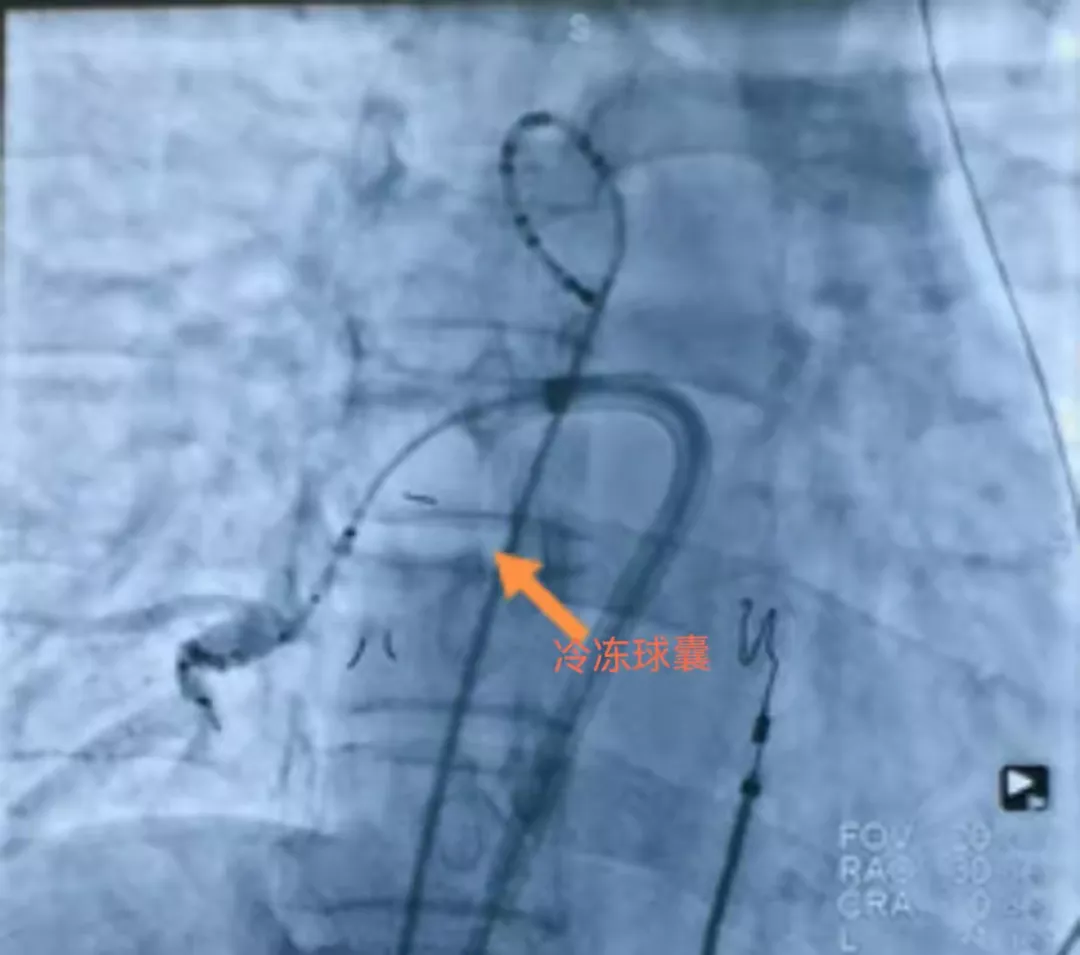

近日,一位76岁的老年男性,主诉“反复心悸、胸闷2年,加重2周”,被诊断为阵发性心房纤颤。在近两年以来,患者因反复不适已经辗转于西安市多家医院就医,但始终没有能解决患者的顽疾,最终来到西电集团医院就诊。心血管内科陈文璐副主任医师作为该患者此次住院的首诊医师,他对患者既往的检查资料(冠脉CTA、心脏彩超、动态心电图、各项检验结果等)进行了详细的整理与研究,并第一时间与心血管内科徐晓辉主任进行沟通,最终决定为患者实施冷冻消融射频手术治疗。由于患者高龄,陈大夫向患者及家属进行充分的手术风险告知后,患者的家属说:“没问题,我相信你,我们听你的!”通过几天的交往过程,患者家属相信这个1.9米的“高大夫”技术实力与他的身高是一样厉害。 在取得患者及家属的高度认可后,陈文璐副主任医师与徐晓辉主任、耿蓬勃副主任一起制定详尽的手术应急预案,备齐手术器械和使用物品,并邀请空军军医大学西京医院的武峰教授前来作阵。 9月17日14:45,手术如期开始,徐晓辉主任、陈文璐副主任医师、耿蓬勃副主任分别在双股静脉进行穿刺,置入2个6F和左1鞘管,将可调弯十级电极送至冠状静脉窦远端、四级电极送至右心室心尖部。成功穿刺房间隔后将Achieve电极送至左上肺静脉,以此为轨道将冷冻球囊分别依次送至左上、左下、右上、右下肺静脉开口处,然后于球囊中冲入N2O气体膨胀球囊封堵肺静脉开口,利用冷冻消融的原理,对病变组织进行治疗,手术历时1.5个小时。患者心脏传导的异常纤维被成功去除,心电监护仪上立即显示出整整齐齐的窦性心律。 术后第一天,76岁的大爷精神矍铄,高兴的说:“心前区再也没有那种咚咚乱跳的难受劲了!”他的笑脸,是对医务人员的技术和服务给予高度的肯定与感激。 房颤冷冻消融术具有创伤小、痛苦低、并发症少、手术时间更短的显着优势。此例手术为首次在西电集团医院成功实施,同时也标志着西电集团医院心内科迈上了房颤冷冻消融的新台阶。 切切实实为患者提供最优质的医疗技术服务,让患者少跑路,少受罪,早治病,治好病,使患者满意,让家属放心。这也是心血管内科在努力践行“病人满意,我就满意,病人好,我就好”提升服务百日行动活动的又一重要体现! 相关链接: 冷冻消融是研究人员继射频消融之后发明的心律失常治疗新技术。其原理是通过液态制冷剂的吸热蒸发,带走组织热量,使目标消融部位温度降低,异常电生理的细胞组织遭到破坏,从而减除心律失常的风险。 大量临床数据显示,和传统射频消融相比,冷冻消融更易于医生操作,缩短了手术时间,治疗有效性高,并减少血栓等严重并发症,降低患者疼痛度。 优势体现: 冷冻消融术是利用冷冻标测和冷冻粘结技术,具有: (1)通过电传导特性的改变可观察消融的有效性; (2)紧贴靶点,防止移位,避免损伤房室传导组织; (3)消融过程中不出现结性心律,使观察房室传导更精确; (4)在标测过程中出现的房室传导阻滞都是可逆的特点,使冷冻消融术在治疗房室结折返性心动过速时与射频消融相比有其无法比拟的优势。 心血管内科供稿